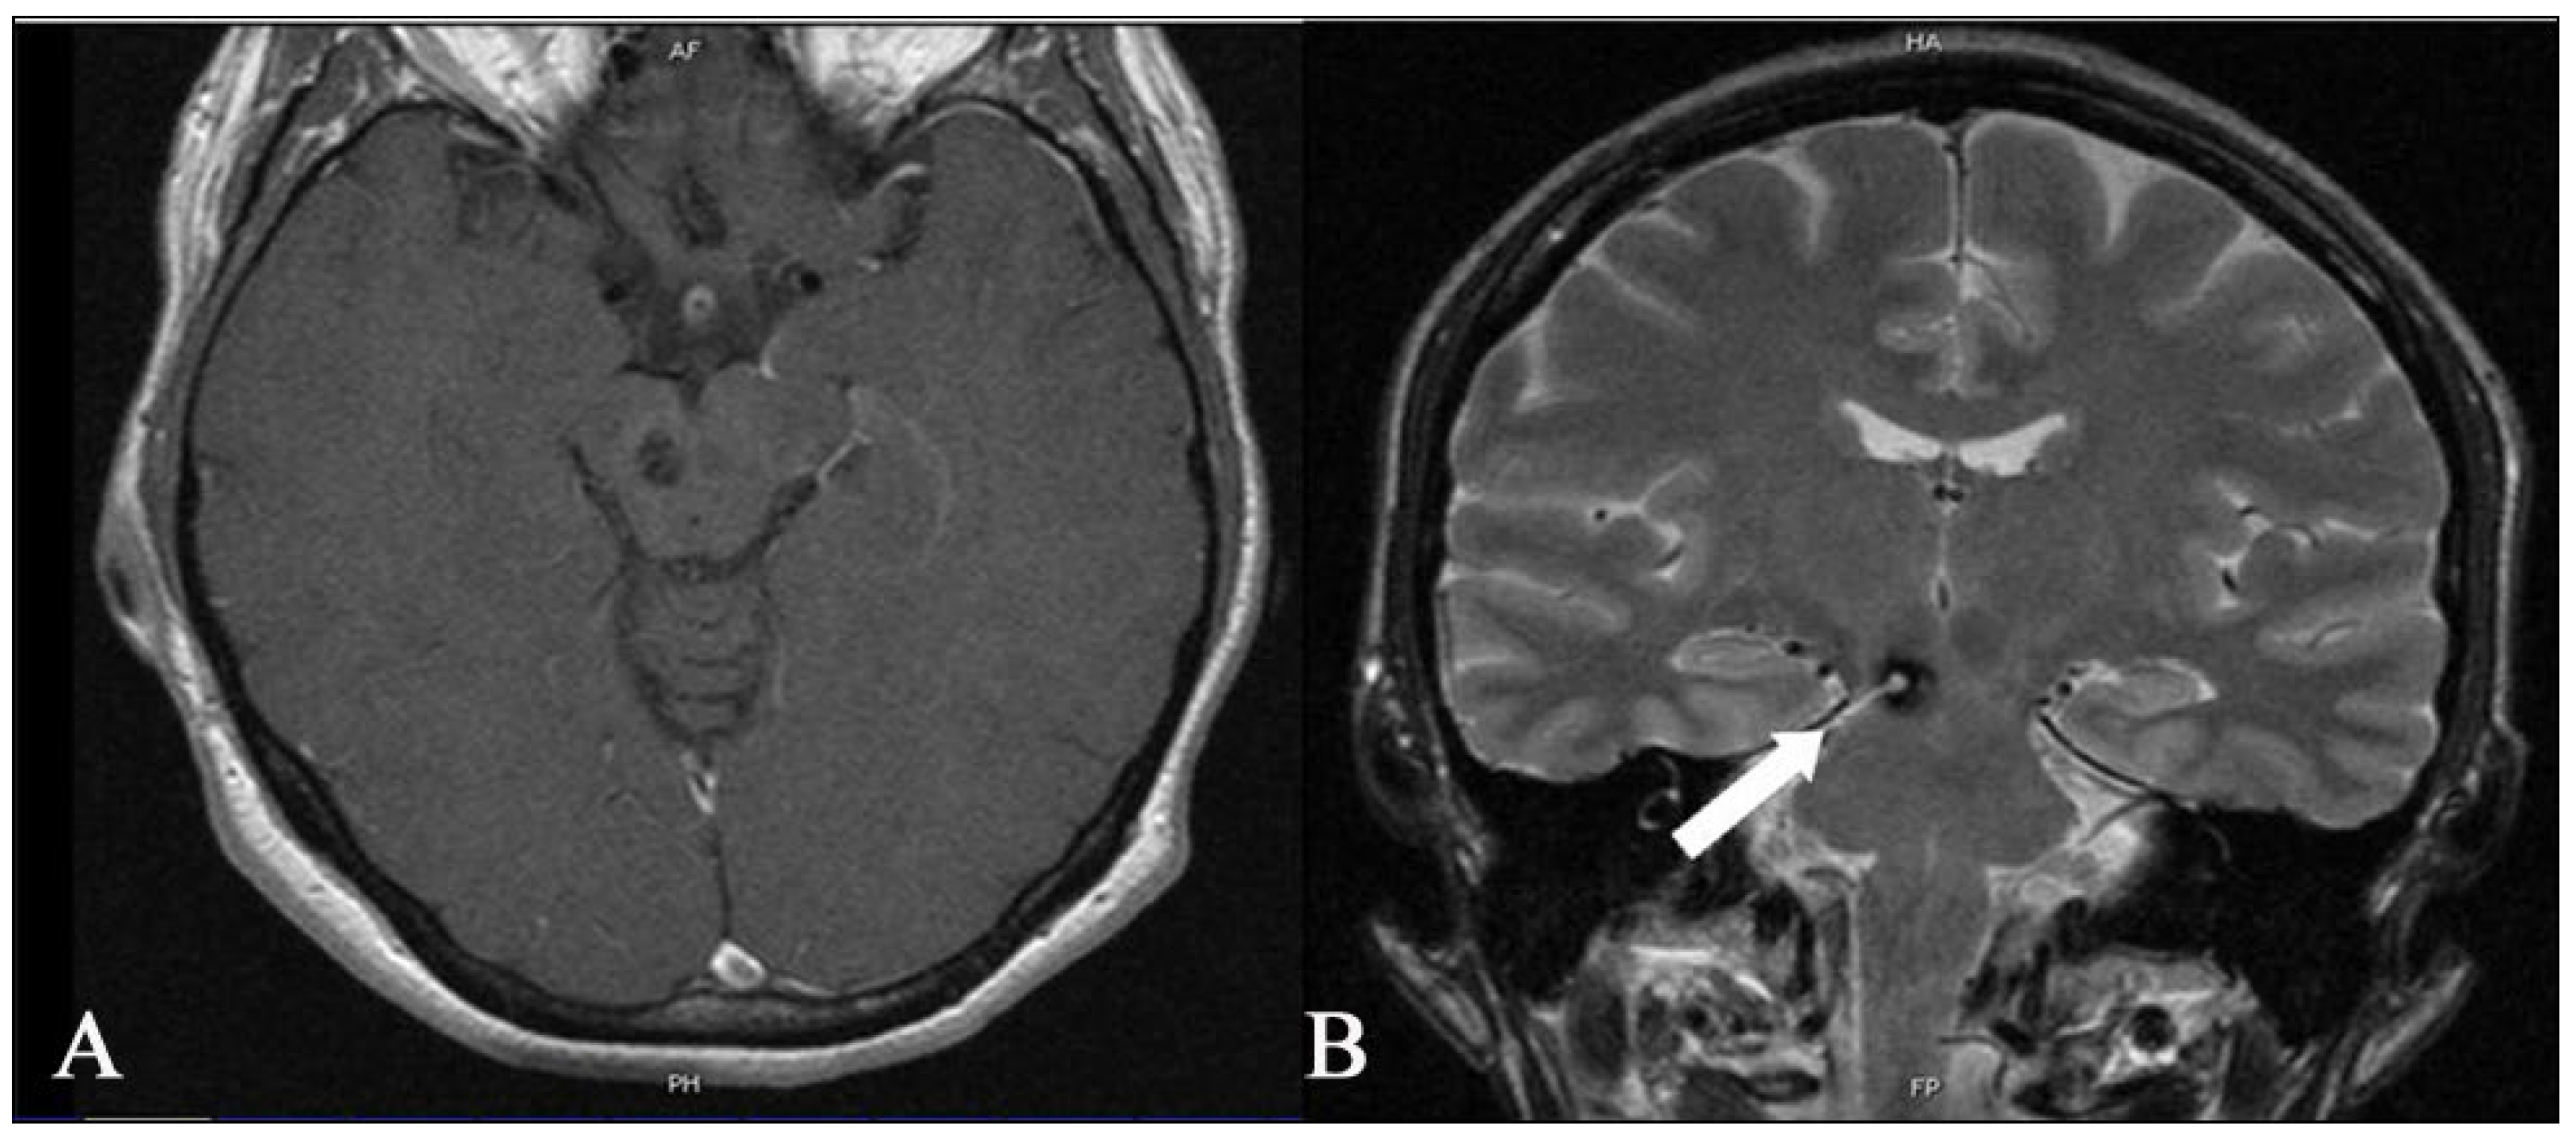

Figure 6. Postoperative axial (A) T1 and coronal T2 images (B) MR show that complete removal of the deep-seated cavernous malformation of the brainstem was achieved. The coronal image on the right shows the entry site into the brainstem (white arrow) through which the cavernoma was accessed. The patient was neurologically stable after surgery. She had no new neurologic deficits after surgery, either in the immediate postoperative period or during the 3-month follow-up.